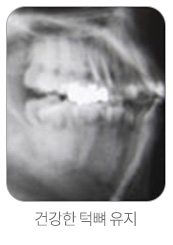

임플란트는 자연치아와 거의 같아, 단단한 음식도 잘 씹을 수 있고 관리정도에 따라 반영구적으로 사용할 수 있으며, 심미적으로도 우수합니다. 소실된 치아 부분에만 식립하기 때문에 다른 치아에 손상을 주지 않고, 틀니의 불편함으로부터 완전히 해방될 수 있습니다. 틀니의 장기 사용은 턱뼈의 퇴화를 가져오기도 하지만 자연치아가 없는 빈자리에 임플란트를 심으면 골이 단단해지고 뼈의 흡수가 줄어들어 건강한 턱뼈를 유지할 수 있습니다.